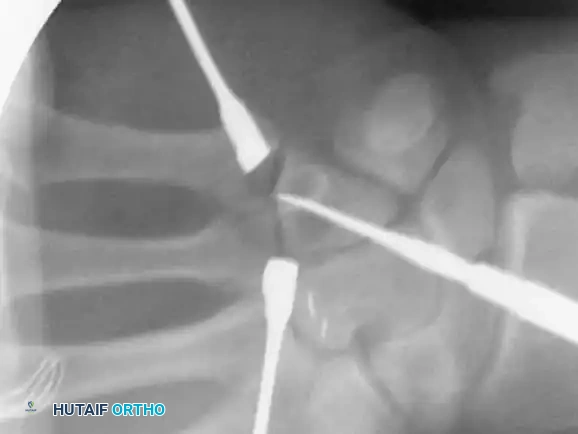

Percutaneous Techniques: Belsky-Eaton Pinning

Sometimes an unstable oblique fracture of a middle or proximal phalanx can be treated by closed reduction and percutaneous pinning. Belsky and Eaton described a highly effective technique for pinning multiple proximal phalangeal fractures without opening the fracture site.

Step-by-Step Technique:

* The fractured phalanx is held reduced with the MCP joint flexed to 90 degrees. This tightens the collateral ligaments, using them as a tension band to align the proximal fragment.

* A single K-wire is drilled from the dorsal aspect of the metacarpal head, passing across the MCP joint and straight down the medullary canal of the proximal phalanx to cross the fracture.

* Crucial Step: The wire must not cross the PIP joint.

* Leave the wire exposed proximally (bent outside the skin) to allow for easy removal in the clinic at 3 to 4 weeks.